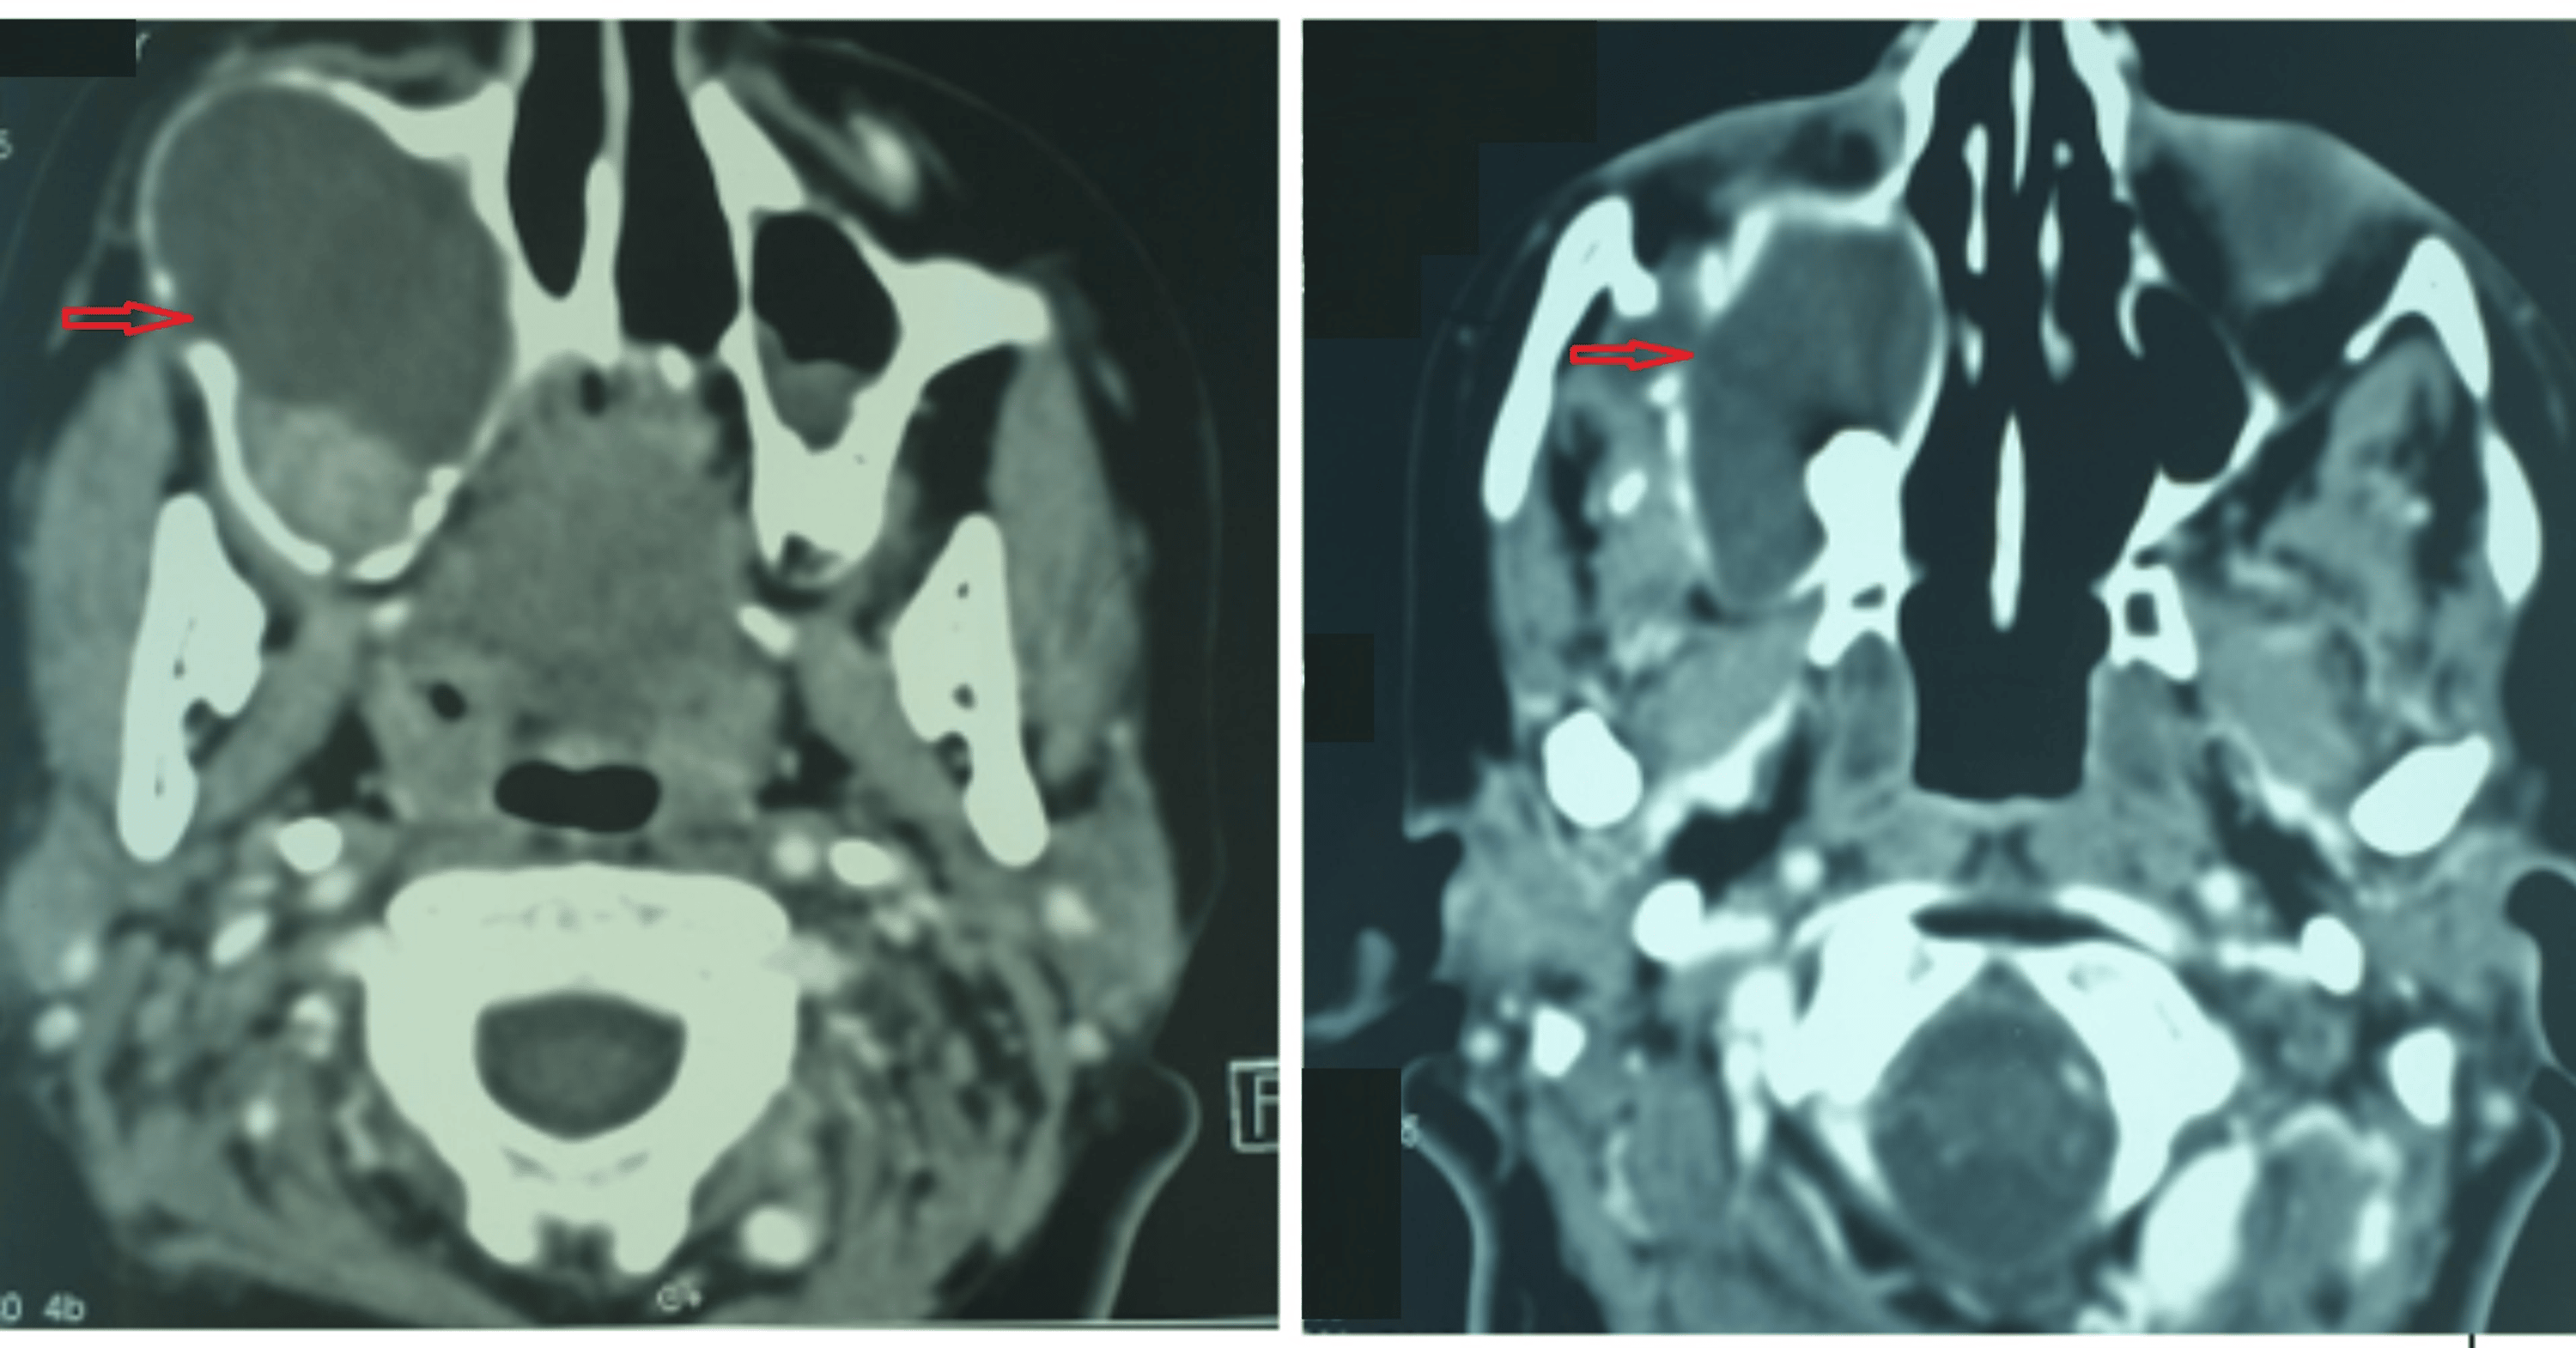

(PDF) Maxillary Sinus Ameloblastoma in Turner syndrome A Comprehensive Ameloblastoma Follow Up Peripheral ameloblastoma may involve soft tissues without invasion or. Ameloblastoma is a benign lesion of the jaws with a locally invasive course and high. Ameloblastoma is the most common benign, but locally destructive, epithelial odontogenic tumour. The most frequently performed treatment option was enucleation plus curettage/peripheral ostectomy in 94 ameloblastomas, followed by. The average period of follow up was 6.2. Ameloblastoma Follow Up.

Cureus Maxillary Sinus Ameloblastoma in Turner Syndrome A Ameloblastoma Follow Up Ameloblastoma is a benign lesion of the jaws with a locally invasive course and high. Ameloblastoma is the most common benign, but locally destructive, epithelial odontogenic tumour. Peripheral ameloblastoma may involve soft tissues without invasion or. The average period of follow up was 6.2 years. Keeping patients informed of the importance of regular follow up is crucial to. Ameloblastoma is. Ameloblastoma Follow Up.

Cureus Maxillary Sinus Ameloblastoma in Turner Syndrome A Ameloblastoma Follow Up Keeping patients informed of the importance of regular follow up is crucial to. Ameloblastoma is a benign lesion of the jaws with a locally invasive course and high. Peripheral ameloblastoma may involve soft tissues without invasion or. The most frequently performed treatment option was enucleation plus curettage/peripheral ostectomy in 94 ameloblastomas, followed by. The average period of follow up was. Ameloblastoma Follow Up.